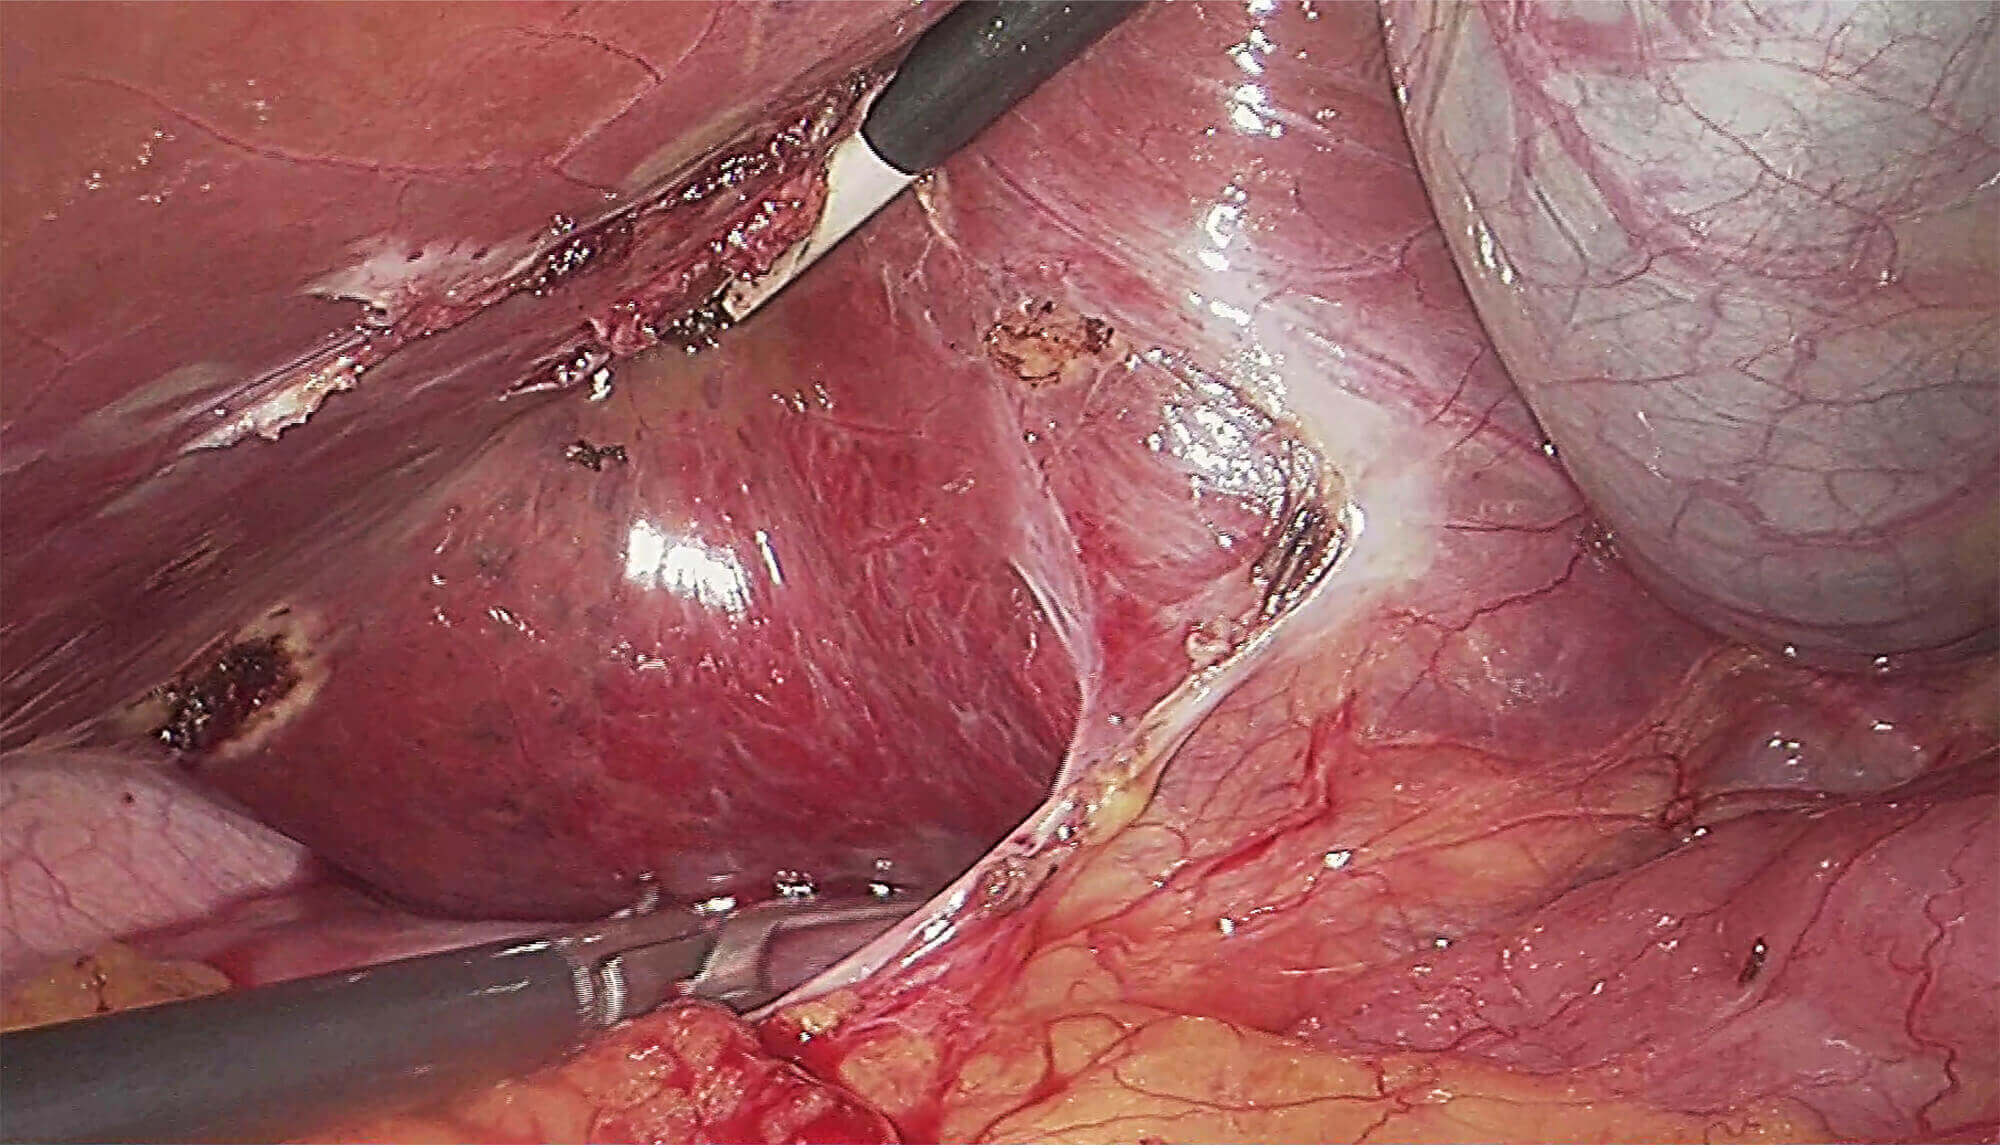

采用3片CMOS图像传感器,输出1920*1080P、60FPS全高清数字信号,提供稳定的腔镜视野,给予术者极佳的视觉体验,让手术更轻松,更精细!

领航微创外科精准诊疗新标准